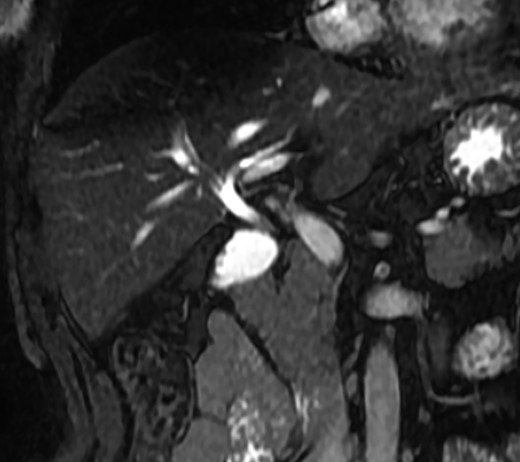

A magnetic resonance cholangiopancreatography (MRCP) confirmed the absence of gallbladder and of the cystic duct and artery (Figs 4–6). No other abdominal anomaly was identified.

MRCP coronal image showing the common bile duct, portal vein, duodenum, liver and other close structures; there is no sign of gallbladder.